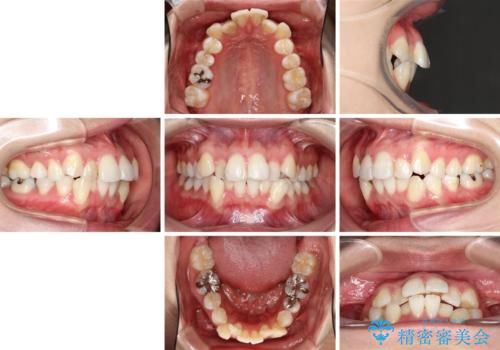

- 前歯のデコボコと上顎の前突感による口の閉じにくさを気にして来院された患者様です。

目立たない装置を希望されたので、上顎が裏側装置のハーフリンガルを選択し、上下左右の小臼歯(計4歯)を抜歯して矯正治療を行うこととしました。